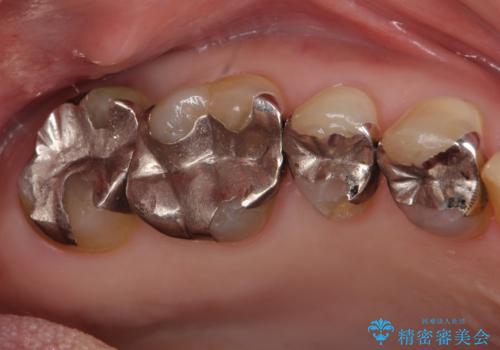

- 詰め物が欠けたとのことで来院されました。

実際は詰め物ではなく歯自体が欠けている状態でした。

銀の詰め物を外し、欠けたところを覆うように新しい詰め物を作成します。